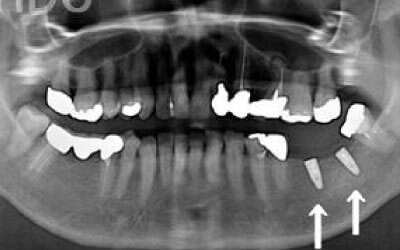

1)ブリッジ

2)歯を大きく削る+支えの歯に1.5倍の力がかかる

3)前後の歯の寿命が著しく減る

ブリッジの支えの歯は、データでは10年以内に68%が抜歯になります。